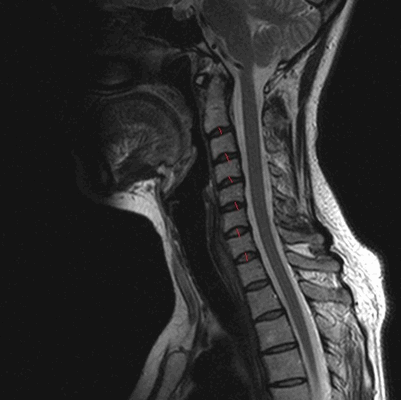

МРТ позвоночника в шейном отделе, оценка высоты дисков (указана красными линиями)